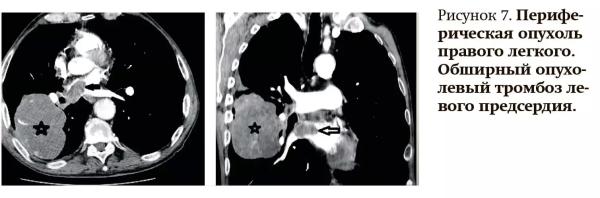

— У пациентки с периферической опухолью в правом легком появились жалобы на одышку, отмечались шумы в левом предсердии, изменения на ЭКГ, выполнена Эхо-КГ, свидетельствующая о выраженной сердечной недостаточности. Вследствие этого была предпринята попытка выполнить плановое МРТ-исследование сердца, однако его пришлось прервать, так как пациентка не смогла выполнять команды, исследование оказалось неинформативным. Принято решение о выполнении КТ с ангиографией, на котором четко увидели признаки обширного тромбоза левого предсердия (см. рис. 7).